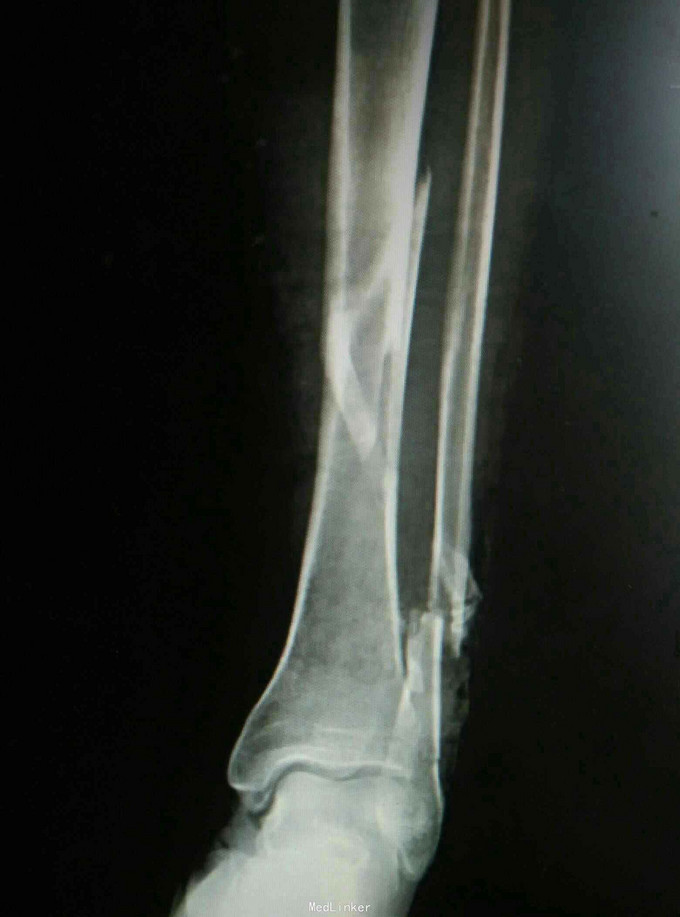

左小腿疼痛畸形,活动受限5小时 患者因骑车摔伤出现左小腿疼痛、畸形,当即出现活动受限无法站立,余未诉特殊不适,急诊摄片提示左胫腓骨远端骨折。

查体:左下肢肿胀畸形,局部可及骨擦感,压痛明显,未见明显张力性水泡,踝关节活动轻度受限,足趾感觉无异常,对侧膝踝关节活动无异常。 辅查:摄片提示左胫腓骨远端骨折。

诊断:左胫腓骨远端骨折 治疗:骨折切开复位内固定